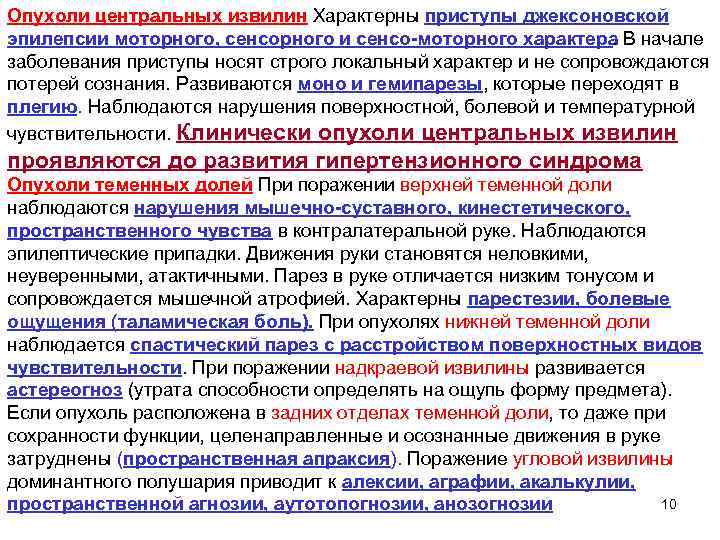

Опухоли центральных извилин Характерны приступы джексоновской эпилепсии моторного, сенсорного и сенсо моторного характера. В начале заболевания приступы носят строго локальный характер и не сопровождаются потерей сознания. Развиваются моно и гемипарезы, которые переходят в плегию. Наблюдаются нарушения поверхностной, болевой и температурной чувствительности. Клинически опухоли центральных извилин проявляются до развития гипертензионного синдрома Опухоли теменных долей При поражении верхней теменной доли наблюдаются нарушения мышечно суставного, кинестетического, пространственного чувства в контралатеральной руке. Наблюдаются эпилептические припадки. Движения руки становятся неловкими, неуверенными, атактичными. Парез в руке отличается низким тонусом и сопровождается мышечной атрофией. Характерны парестезии, болевые ощущения (таламическая боль). При опухолях нижней теменной доли наблюдается спастический парез с расстройством поверхностных видов чувствительности. При поражении надкраевой извилины развивается астереогноз (утрата способности определять на ощупь форму предмета). Если опухоль расположена в задних отделах теменной доли, то даже при сохранности функции, целенаправленные и осознанные движения в руке затруднены (пространственная апраксия). Поражение угловой извилины доминантного полушария приводит к алексии, аграфии, акалькулии, 10 пространственной агнозии, аутотопогнозии, анозогнозии